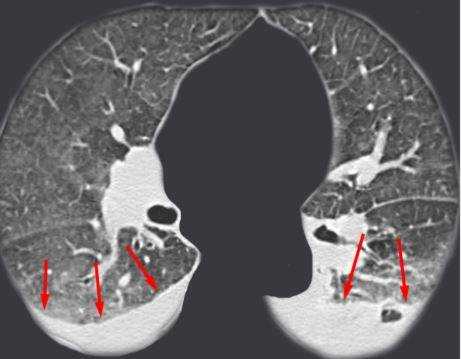

Диагностика метастазов в легкие: КТ и рентгенография

Компьютерная томография — один из самых чувствительных и распространенных методов диагностики метастазов в легкие. Это исследование позволяет выявить очаги опухоли меньше 1 мм в диаметре. Более чувствительным и специфичным методом является только ПЭТ/КТ, но он меньше распространен, дороже и сложнее в применении.Для выявления мелких очагов лучше использовать спиральную компьютерную томографию. Чтобы определить метастазы в легкие, контрастное усиление не является обязательным, но может быть полезным для дифференцировки легочных сосудов и лимфоузлов при их вторичном поражении.

КТ-ПРИЗНАКИ МЕТАСТАЗОВ В ЛЕГКИЕ

Метастазы чаще всего представлены узловыми образованиями в легочной ткани вне строгой связи с легочными артериями или венами. Для них характерны следующие КТ-признаки:

Вторичные узлы гематогенного характера чаще всего имеют ровные края, четкие контуры и однородную структуру. Возможны изменения структуры опухоли вследствие кровоизлияния в паренхиму, обызвествлений, некроза центральной части узла, а также рубцов. Края узла могут стать нечеткими, расплывчатыми, если опухоль провоцирует отек легочной паренхимы, либо «лучистыми», если имеет место опухолевый лимфангиит.

Множественные гематогенные вторичные узлы при раке почки, компьютерная томография (КТ).